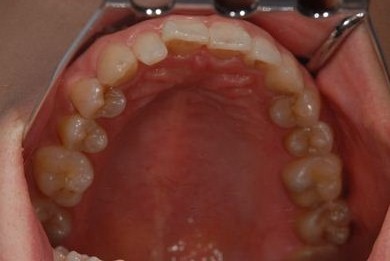

治療前

• 治療前